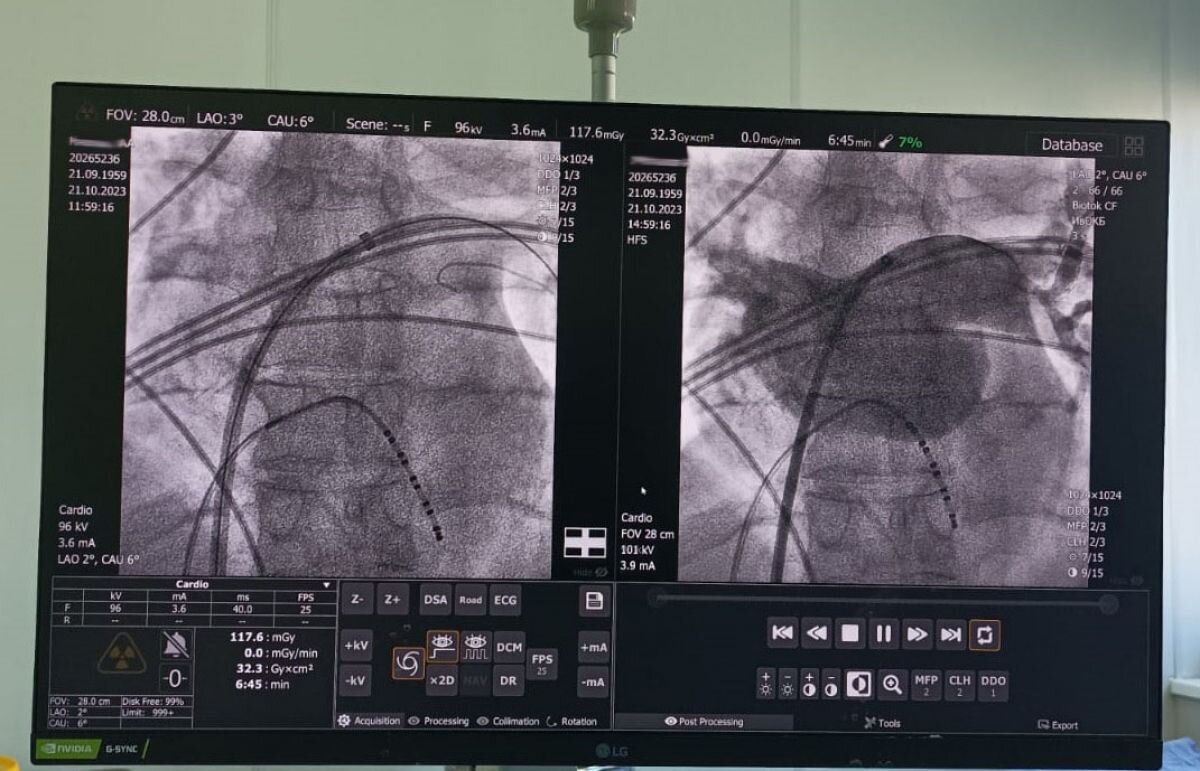

В Ивановской области научились выполнять криоизоляцию устьев лёгочных вен. О новом достижении Ивановской ОКБ рассказал Антон Андреев, заведующий кардиохирургическим отделением.

«Операция называется криоизоляция устьев лёгочных вен и выполняется эндоваскулярно («закрытым» способом) при помощи специальных электродов-катетеров. Используется она для лечения опасного и массово распространённого заболевания - мерцательной аритмии» - пояснил специалист.

Выполнять криоизоляцию ивановские кардиохирурги смогли только после появления в больнице нового дорогостоящего оборудования и других расходных материалов. Зато спустя всего день – два пациенты уже выписываются домой.